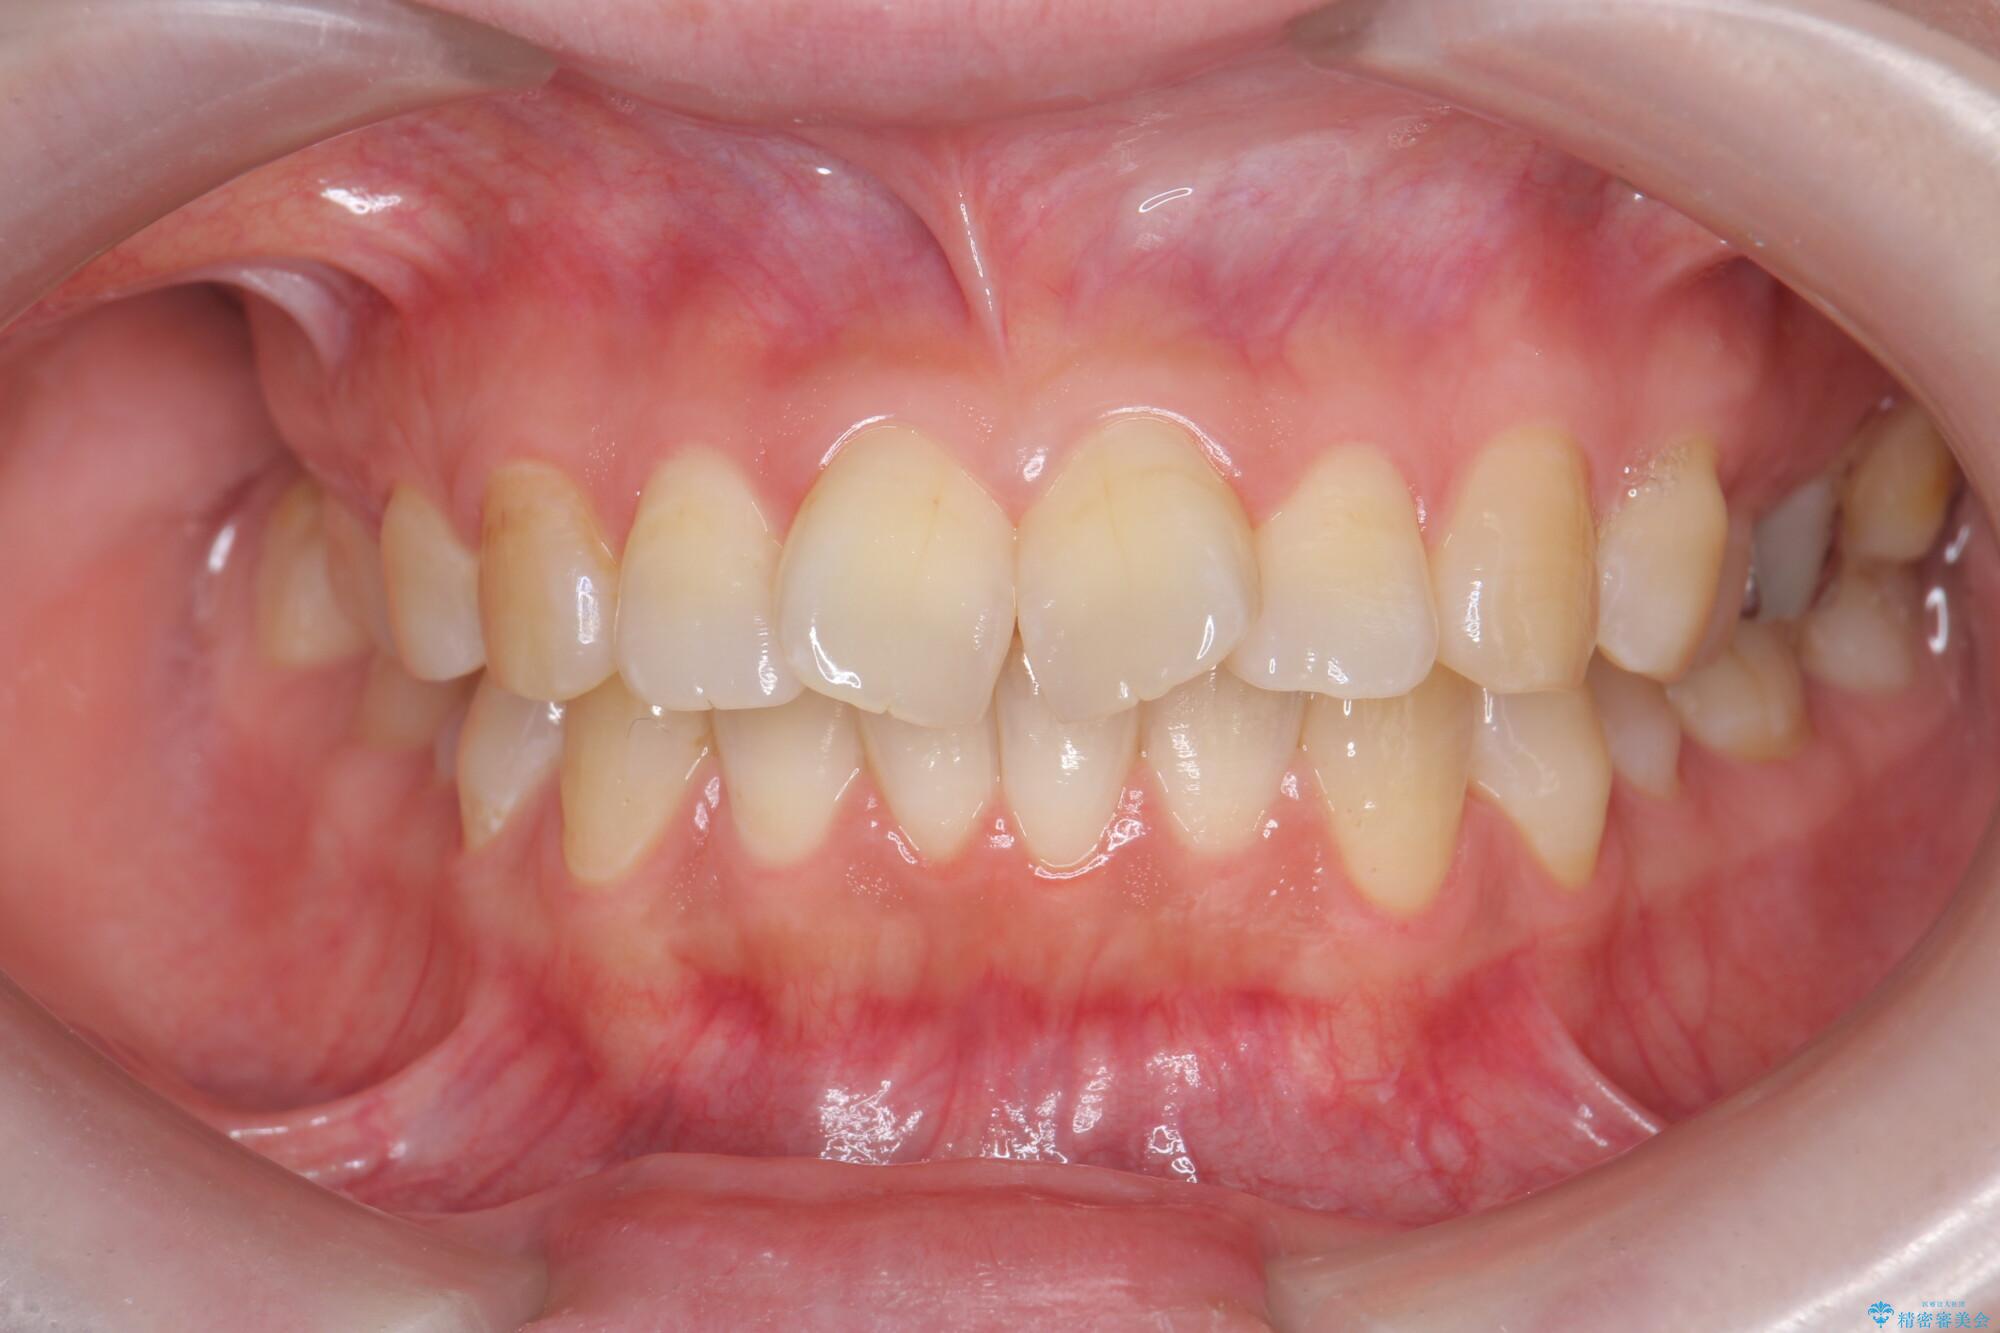

治療前

傾いた前歯、インビザラインで改善 治療前画像 傾いた前歯、インビザラインで改善 治療前画像 傾いた前歯、インビザラインで改善 治療前画像 傾いた前歯、インビザラインで改善 治療前画像